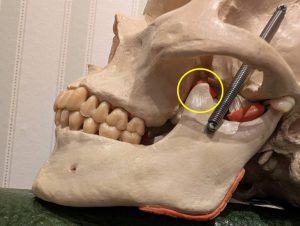

●下顎を持ち上げて噛む筋肉(閉口筋)は、第二大臼歯の後方の下顎角から頬骨の間に「咬筋」という筋肉が深層と浅層で二重に付着しています。またもう一つの大きな筋肉で下顎骨の関節頭の前にある筋突起から頬骨の中を通ってこめかみの上から耳の穴の後ろまでの側頭部前面に扇状についているのが「側頭筋」です。この2つが顎をかみしめる力を発する筋肉です。

そのため筋肉付着部の大臼歯部分が一番力が入りやすい状態のため、両側大臼歯を噛ませることが非常に大事になります。